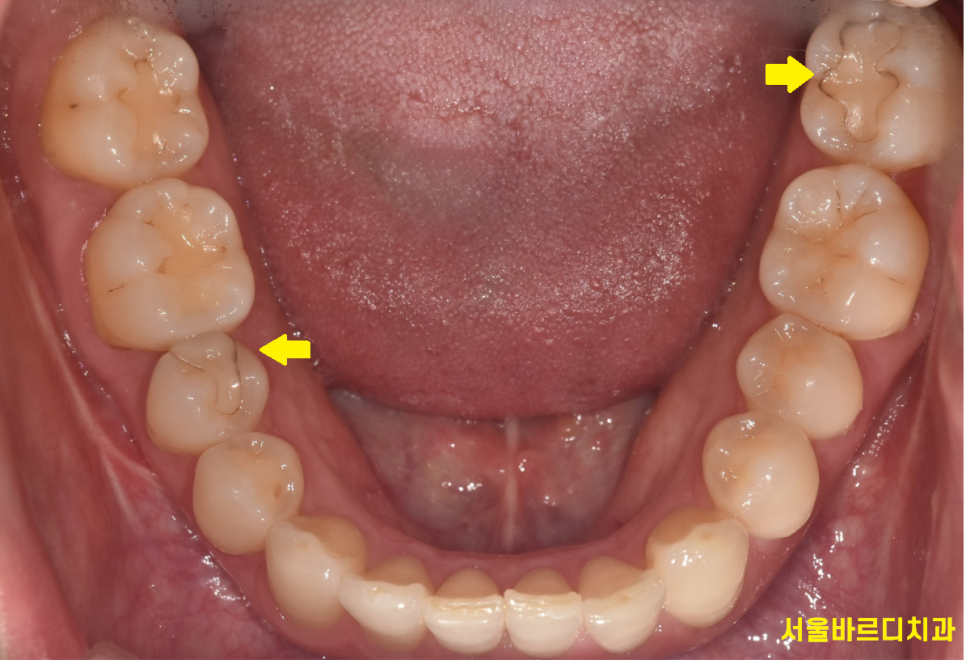

치실을 사용하지 않으면 치아 사이 충치가 생길 수 있고

이럴 경우 인레이 치료를 하게 됩니다.

특히 아래 치아를 치료할 때요!